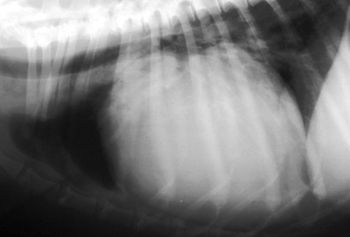

The electrocardiogram (ECG) is a commonly employed diagnostic tool to help in the evaluation of cardiac arrhythmias, to help detect cardiac chamber enlargement, and to identify electrolyte abnormalities.

Echocardiography has emerged as the most valuable non-invasive tool for evaluation of cardiac structure, function, blood flow patterns, and has greatly diminished the need for diagnostic cardiac catheterizations and angiocardiography in many cases.